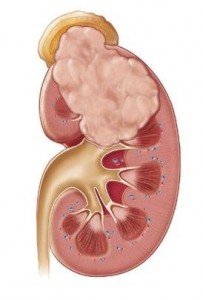

Рак в реальный момент это ужасная и непредсказуемая. Есть сотки различных видов данного заболевания, а именно к ним относится рак почки, который считается самым сложным. Появляющиеся конкретно в почках томные опухоли не лечатся лучевой терапией и не подаются медикаментозному исцелению. Но, не глядя на это, исцеление рака почек полностью может быть. Самое малеханькое количество побочных эффектов дает так именуемая таргетная терапия, результатом от которой нездоровой может избавиться от заболевания раз и на всегда.

Рак в реальный момент это ужасная и непредсказуемая. Есть сотки различных видов данного заболевания, а именно к ним относится рак почки, который считается самым сложным. Появляющиеся конкретно в почках томные опухоли не лечатся лучевой терапией и не подаются медикаментозному исцелению. Но, не глядя на это, исцеление рака почек полностью может быть. Самое малеханькое количество побочных эффектов дает так именуемая таргетная терапия, результатом от которой нездоровой может избавиться от заболевания раз и на всегда.